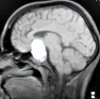

Pituitary CT scan.

Компьютерная томография (КТ) гипофиза вместе с МРТ является основным методом визуализации аденомы гипофиза (пролактиномы, соматотропиномы, пролактокортикотропиномы, пролактосоматотропиномы), а также неактивных («молчащих») гормональных опухолей. КТ гипофиза оценивает топографию, размеры желез; наличие дополнительных образований, их размеры и структура (сплошные, кистозные), распространяющиеся за пределы турецкого седла, прорастание в костные структуры и твердые оболочки мозга. При выполнении компьютерной томографии гипофиза рекомендуется использовать улучшенное разрешение и контраст.